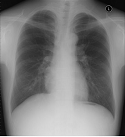

一般撮影

多くの方が一度は受けられたことがあると思いますが、右図が胸部正面X線写真です。この写真一枚で肺の状態から、心臓、大動脈、食道、肝臓等の異常が感知できます。X線写真としては頭部から指先足先まであらゆる部位の撮影をします。以下にご紹介します特殊撮影に対して一般撮影と呼ばれています。打撲での骨折の確認はもちろん、腹痛や肺炎等様々な病変や怪我の確認に用いられます。